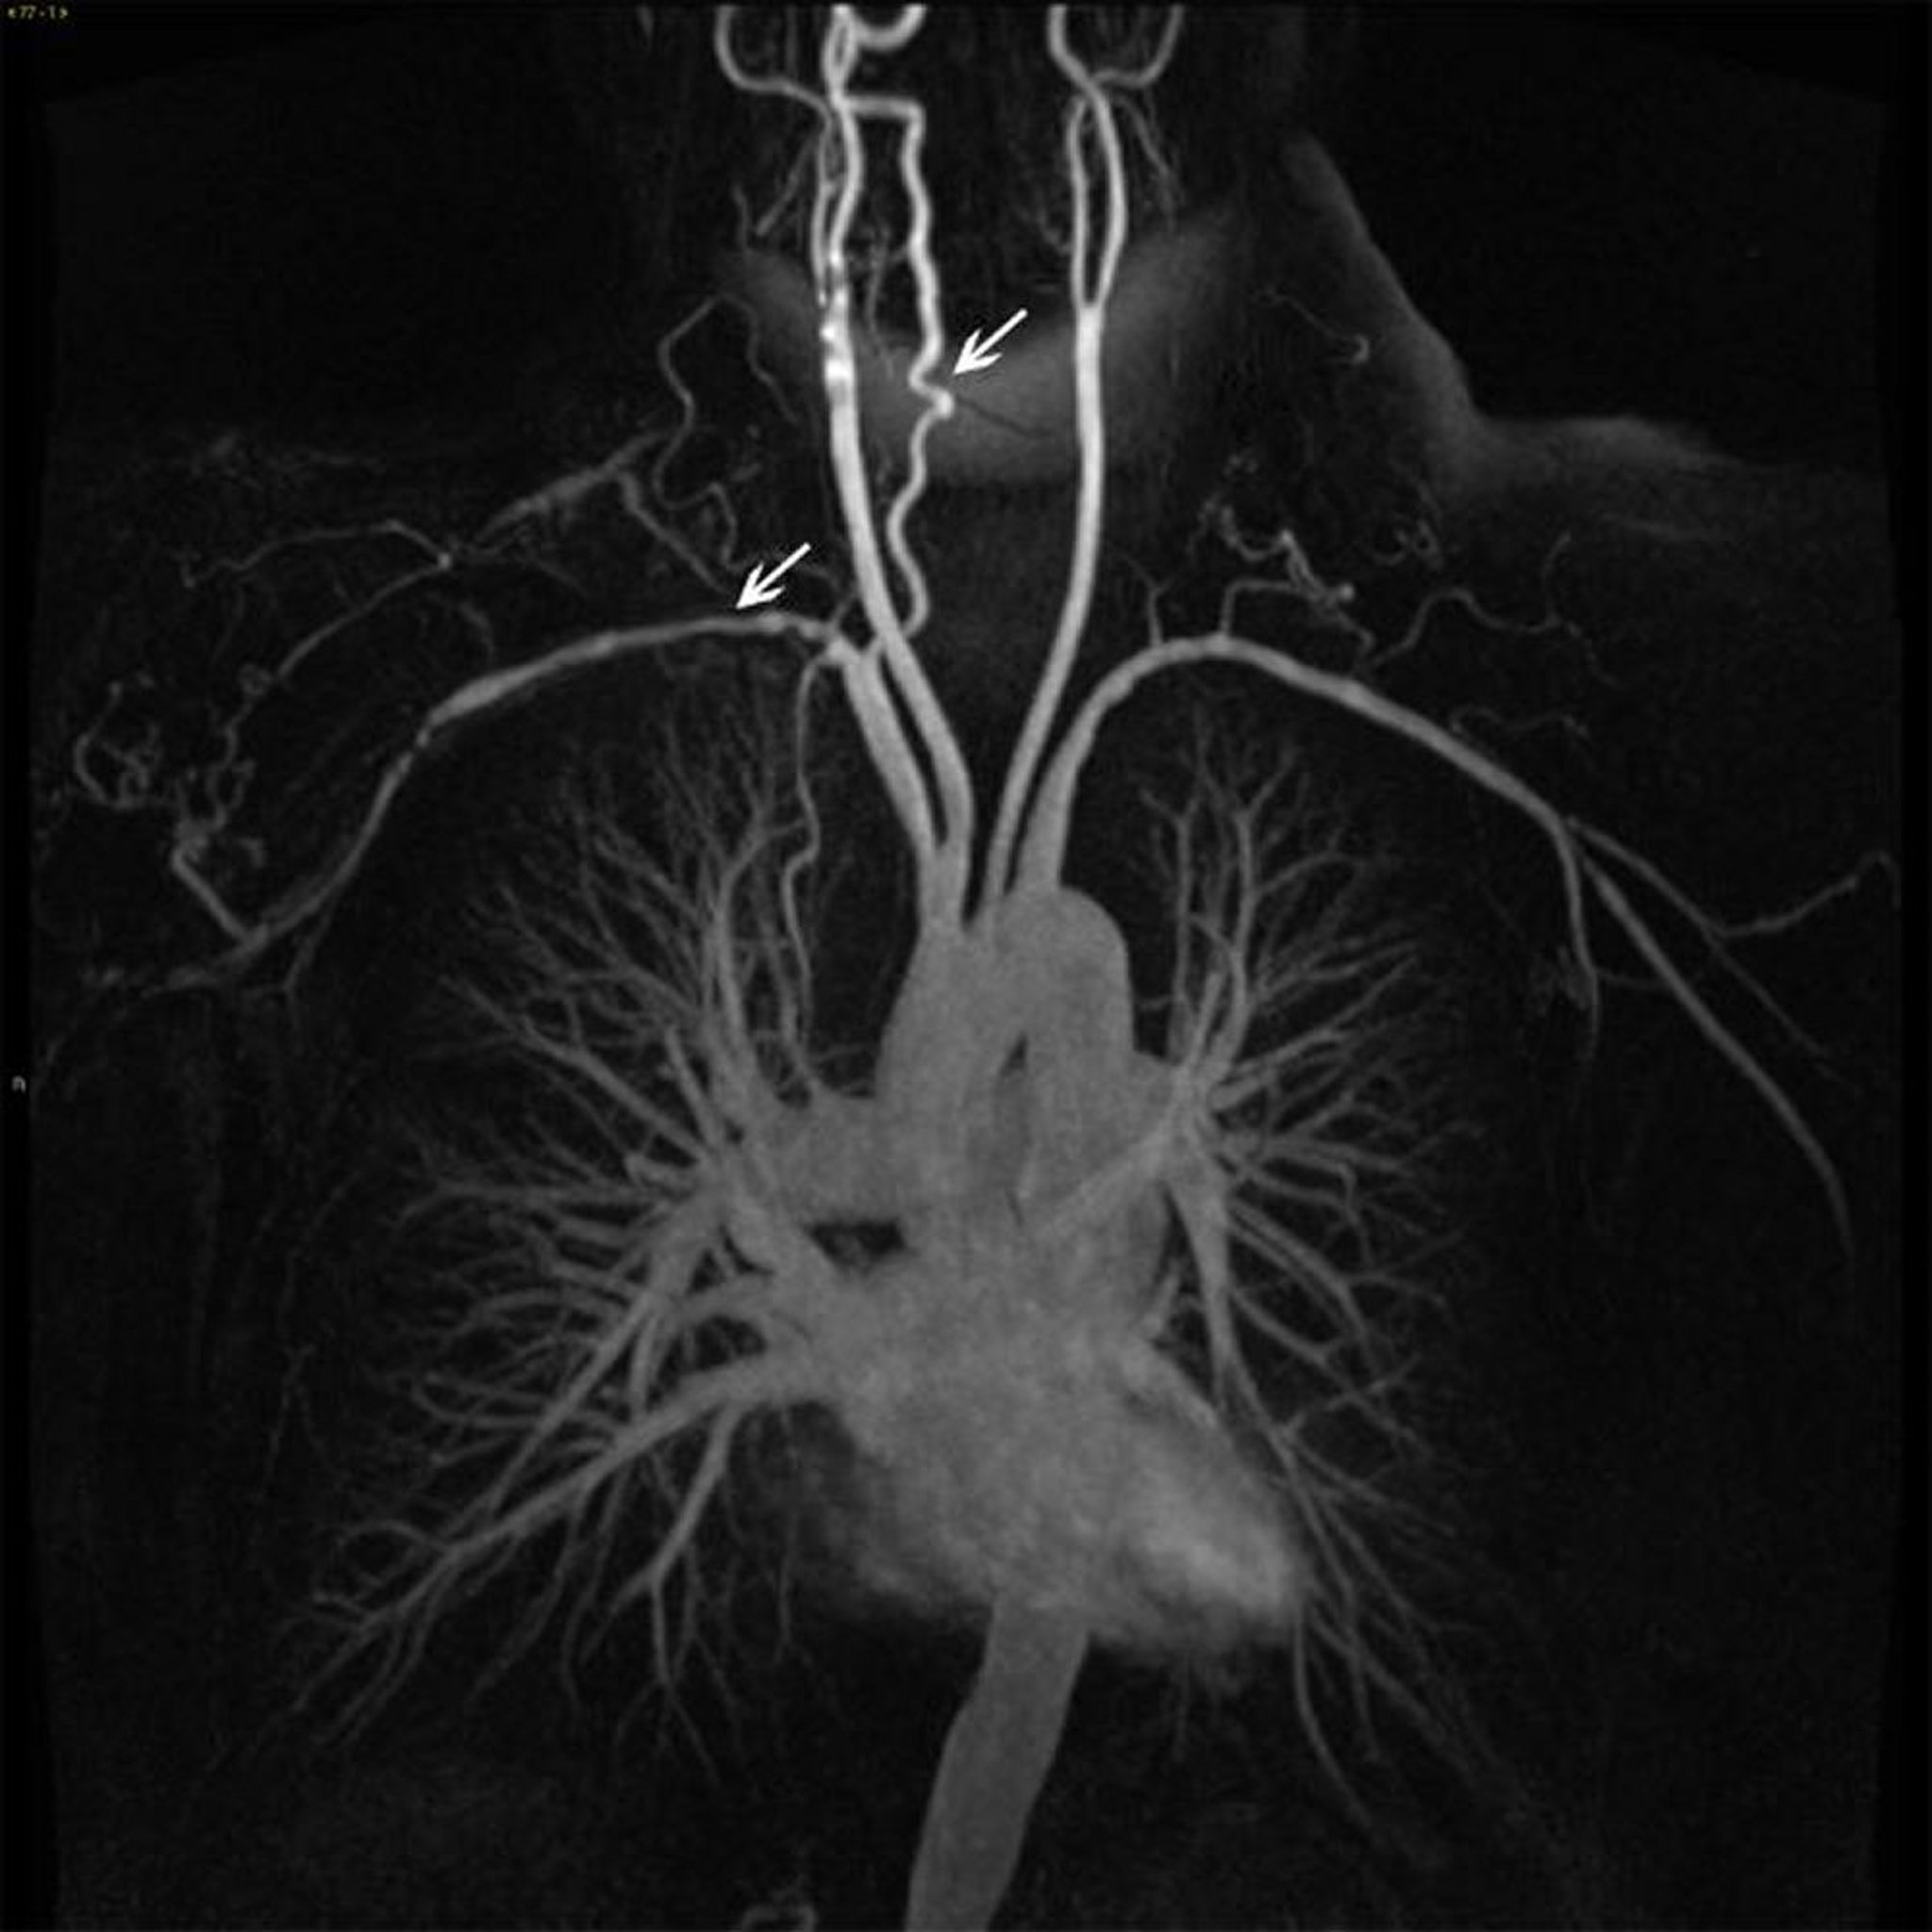

Ramos da aorta torácica ascendente em um paciente com arterite de Takayasu

Essa imagem mostra a irregularidade e o estreitamento mural (setas brancas) em vários ramos da aorta ascendente.